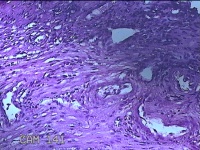

宫腔粘连带

标本名称

大体所见

灰白暗红色不规则碎组织1.3x1.2x0.3cm一堆。

图3